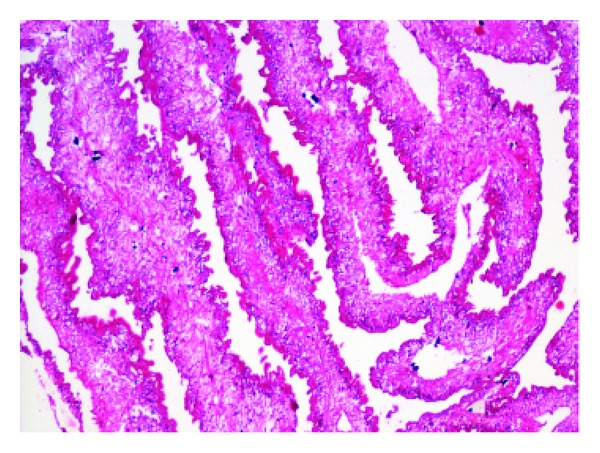

Figure 2.

Cysticercus cellulosae (H&E, ×100).

On cytology, fragments of bluish fibrillary material with interspersed small nuclei were seen (Figure 1). Thick blue spherules within the substance of the fibrillary material gave a honeycomb appearance. Mixed inflammatory cells consisting of neutrophils, eosinophils, lymphocytes, and histiocytes were seen surrounding the fibrillary material. A diagnosis of parasitic material was offered on cytology. This material was excised and sent for histopathological examination. The parasite cysticercus cellulose was seen in the tissue section with extensive mixed inflammatory cell infiltrate in the surrounding tissue (Figure 2). A final diagnosis of subcutaneous cysticercosis was made. The patient also received oral antihelminthic therapy and is doing well.